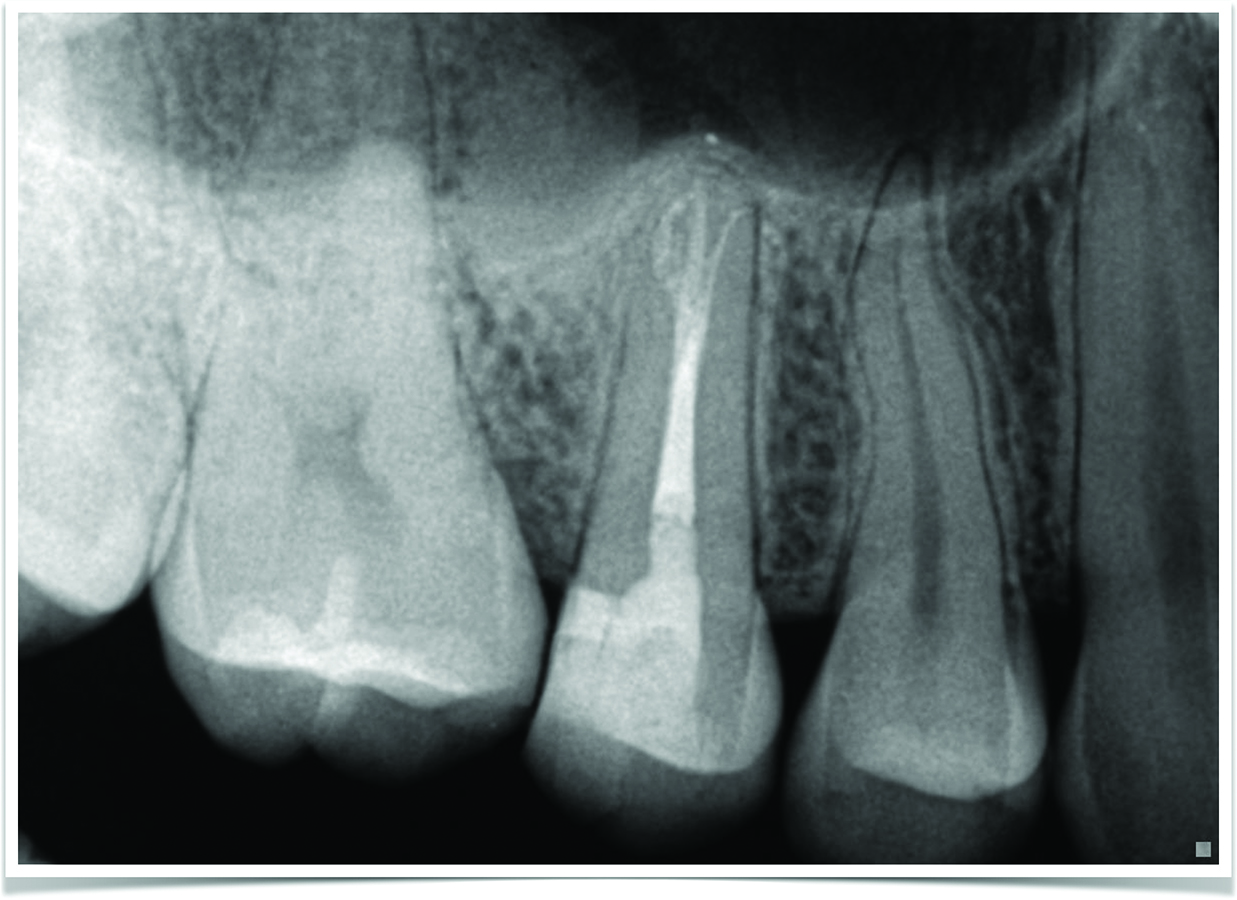

Successful Endodontic Management Using Er,CrYSGG Laser Disinfection of Laser Endodontic Disinfection Root canal treatment is the most effective and widely used method for controlling infection, promoting periapical healing, and. The efficacy of laser therapy applications in root canal disinfection with or without various irrigants protocols remains. Nd:yag laser (1064 nm) has been the most widely investigated laser for. Conventional laser use inside the root canal as an additional disinfection method;. Laboratory. Laser Endodontic Disinfection.